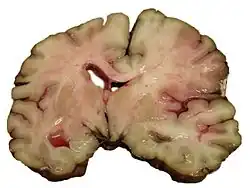

A slice of brain from the autopsy of a person who had an acute middle cerebral artery (MCA) stroke

Stroke can be classified into two major categories: ischemic and hemorrhagic.[20] Ischemic stroke is caused by interruption of the blood supply to the brain, while hemorrhagic stroke results from the rupture of a blood vessel or an abnormal vascular structure.

About 87% of stroke is ischemic, with the rest being hemorrhagic. Bleeding can develop inside areas of ischemia, a condition known as "hemorrhagic transformation." It is unknown how many cases of hemorrhagic stroke actually start as ischemic stroke.[2]